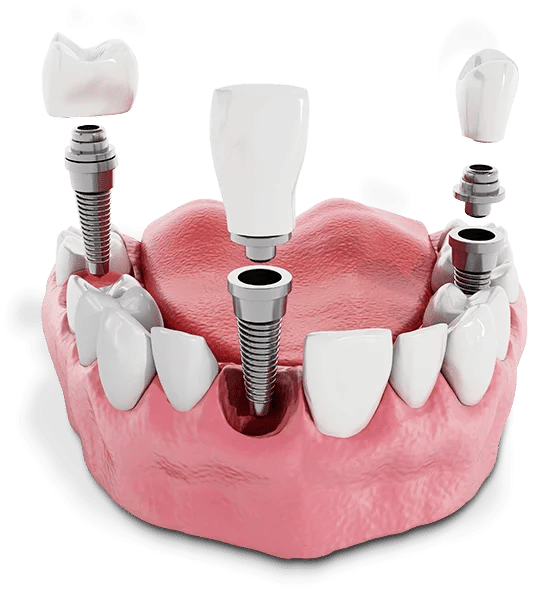

Dental implants are a modern and long-lasting solution for replacing missing teeth. They consist of a small titanium post that is surgically placed into the jawbone, acting as an artificial tooth root.

Once the implant has integrated with the bone, a custom-made crown, bridge, or denture is attached on top, restoring both the appearance and function of the missing tooth.

A single missing tooth

Multiple missing teeth